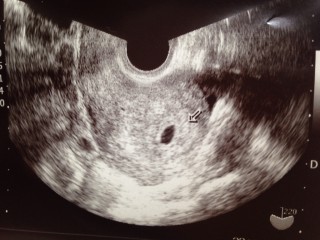

6w0dです! 一週間前の検診よりも大きくはなっていましたが 赤ちゃんはまだ確認できませんでした。 6wにしては小さいそうです。 心配(..) 次は1週間後! 赤ちゃん確認出来ますように!!